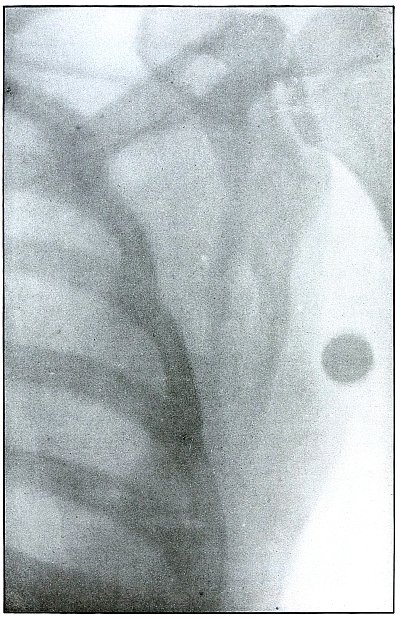

PELVIS.

Plate 46.

[Pg 103]

Rifle—Plate 46.

PELVIS.

Gunshot Wound of the Pelvis,

with Lodgment of the Missile in the Abdomen.

The course of the bullet was from behind forward, striking the crest

of the ilium, on which it was deflected, and spattering off some lead

fragments. The slight penetration indicates a velocity of extremely

long range and a striking energy lessened by ricochet.

The irregular outline of the shadow of the projectile shows its

deformity, and the blurred outline indicates intra-abdominal movement

with respiration.

While the missile, as revealed by its shadow, is not a shrapnel ball,

the distribution of lead particles is more suggestive of a shrapnel

than of a rifle projectile, and the ballistic conditions are more

characteristic of the former than of the latter.

There was no abdominal reaction; the invasion of the abdomen was

revealed by the radiograph.

The treatment in such cases is noninterference unless subsequent

developments furnish definite indications.